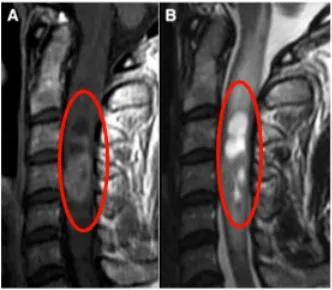

怀着希望,礼小姐前往德国,数日后接受Krauss教授主刀的手术。在常规体感诱发电位监测下,教授采用后方入路,在确保无任何神经损伤的前提下成功全切肿瘤。

手术效果显著,术后12天复查证实肿瘤完全切除,术后水肿基本消失,术前颈椎疼痛症状逐渐缓解。术后两周礼小姐顺利出院,一个月后快速恢复并重返正常生活。